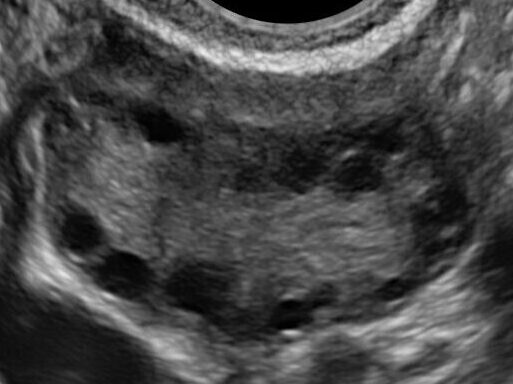

エコー画像:

卵巣に小さな卵胞(黒丸⚫️)がたくさん見える

PCOSの状態をひと言でいえば、卵巣の中で卵胞(卵子の入った袋)が成長しきれず、「出口で渋滞を起こしている」状態です。2)

通常、毎月1つの卵胞が「代表」として選ばれて排卵されますが、PCOSの方は多くの卵胞が同時に育とうとして、結果として誰もゴール(排卵)にたどり着けなくなります。

- 卵巣所見(2.):両側卵巣に多数の小嚢胞が見られ、少なくとも一方で2〜9mmの卵胞が10個以上